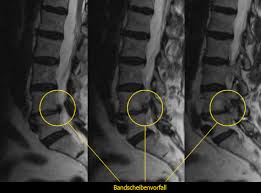

Wird ein Bandscheibenvorfall zwischen L5S1 früh diagnostiziert so ist eine rein konservative Therapie in den meisten Fällen vollkommen ausreichend. Die meisten Menschen mit einem Bandscheibenvorfall im Lendenwirbelbereich werden konservativ behandelt das heißt ohne Operation. Ich möchte mal im kurzen meinen Leidensgeschichte wiedergeben.

Eventuell kann auch eine gezielte Spritze an die Nervenwurzel zur lokalen Abschwellung sinnvoll sein. Wichtig ist dass eine Bettruhe und körperliche Schonung verhindert werden. Vor allem bei einem frischen oder wenig ausgeprägten Bandscheibenvorfall zwischen L5S1 können konservative Behandlungsmethoden beispielsweise spezielle Übungen und Physiotherapie hilfreich sein.